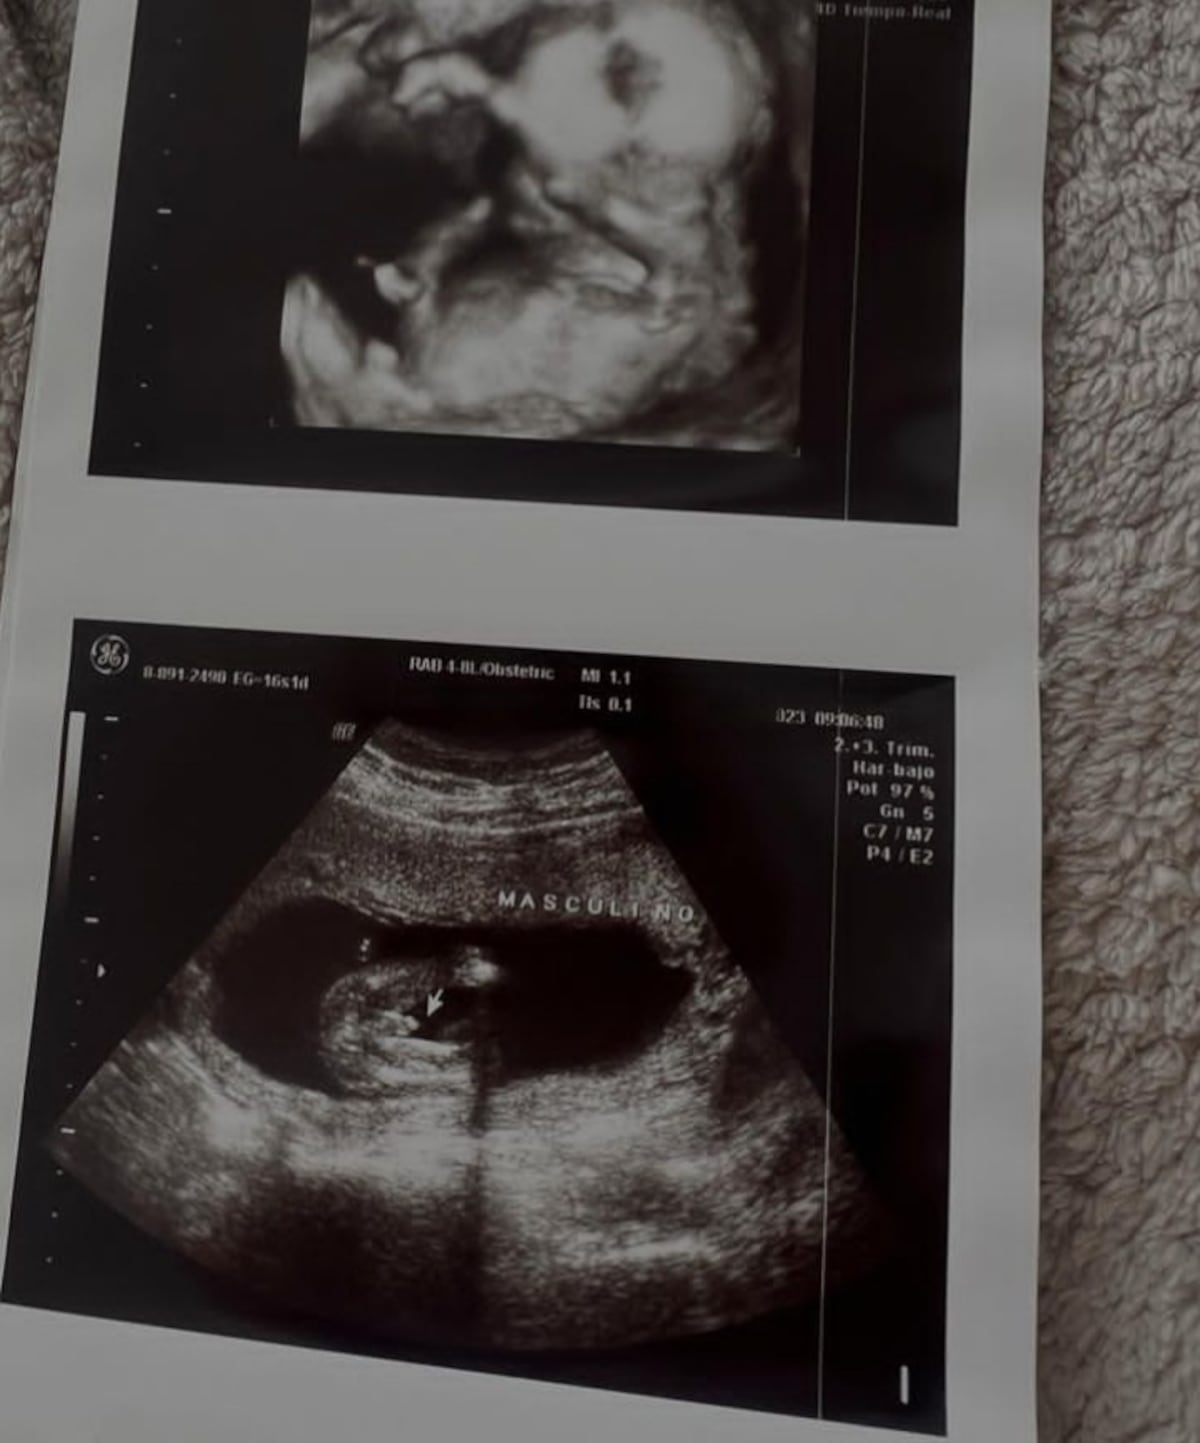

Además de mostrar los ultrasonidos del bebé, enseñó un lindo par de medias que ya le compró.